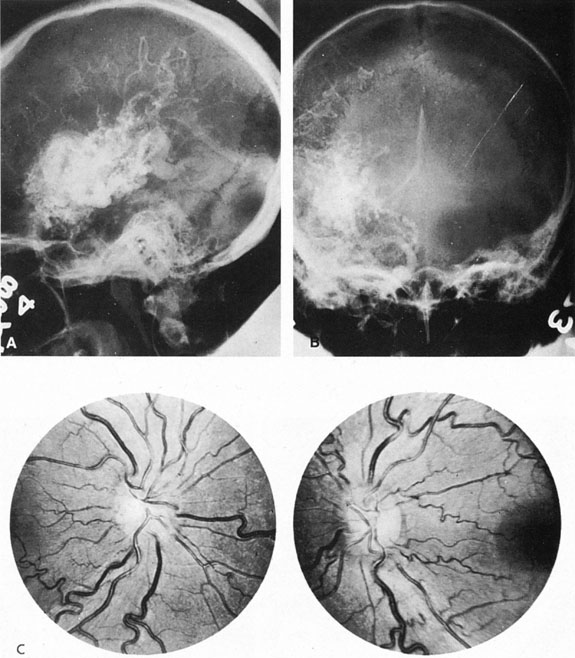

Fig. 7. Supratentorial arteriovenous malformation in a 28-year-old woman with a history of focal motor seizures for many years and a recent subarachnoid hemorrhage. A: Lateral projection carotid arteriogram demonstrating a huge deep hemispheral arteriovenous malformation. B: Frontal projection. C: Fundus photograph showing anomalous tortuous vasculature in each eye. No retinal arteriovenous shunt was detectable.